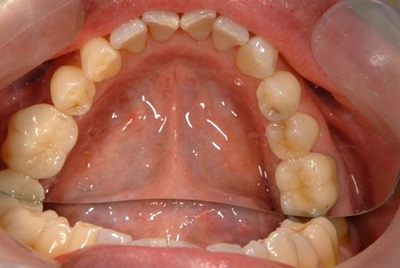

術前口腔内